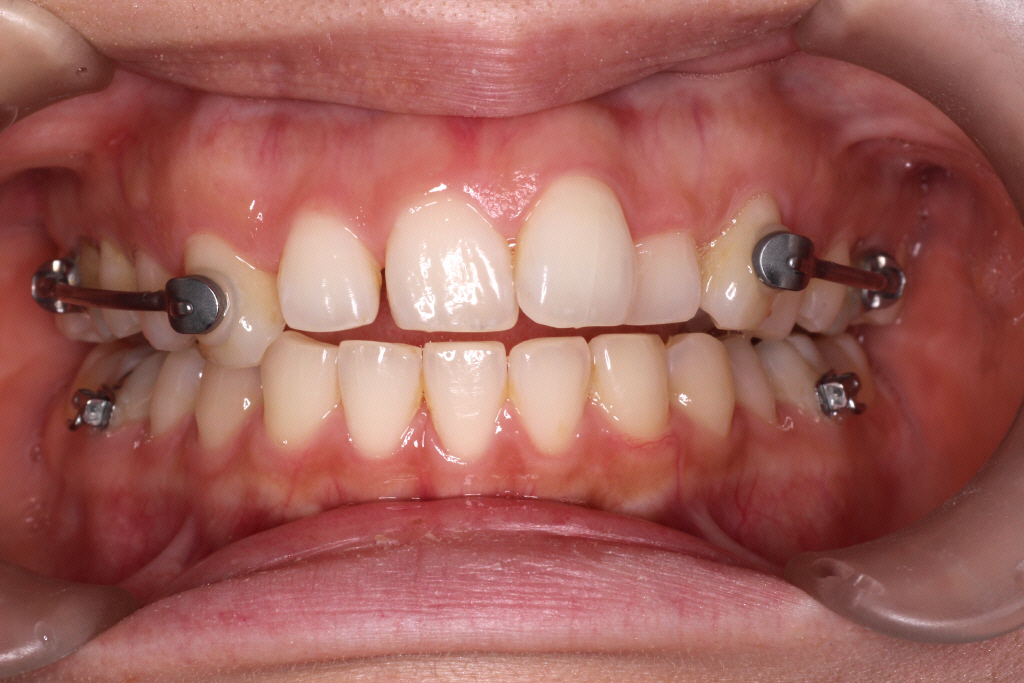

こちらが初診時の口腔内写真です。

上の歯と下の歯の中心がずれています。

また、通常「下の歯2歯に対し上の歯が1歯」というのが正常な歯並びですが

この患者様の場合、右側のみ下の歯が1歯に対し上の歯が1歯になっている事が分かります。

つまり右の咬み合わせは出っ歯の咬み合わせなので上の歯を後ろに下げる必要があります。

診断:上顎前突・上顎前歯部叢生・下顎左側切歯先天欠如